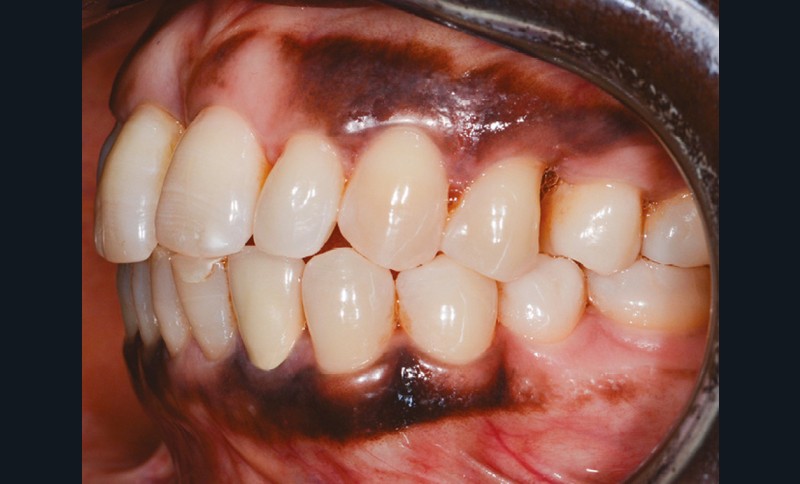

L’observation clinique après traitement parodontal initial révèle, au niveau interarcade, des rapports de classe I molaire bilatéraux associés à des rapports de bout à bout incisif. Dans la dimension verticale, elle présente une légère infraclusion antérieure. On ne note pas d’anomalie de la dimension transversale (fig. 3 à 5). À l’examen intra-arcade, on constate des diastèmes maxillaires interincisifs (1 mm), en distal de 13 (0,5 mm) et de 24 (1 mm) ainsi que des malpositions unitaires (linguoversion de 12, rotation mésio-vestibulaire disto-linguale de 24). À la mandibule, on observe une couronne céramométallique au niveau de 32 plus large de 1,5 mm que les autres incisives ainsi qu’une rotation mésio- linguale de 35 (fig. 6 à 8). En diduction, on note une interférence au niveau de 24.